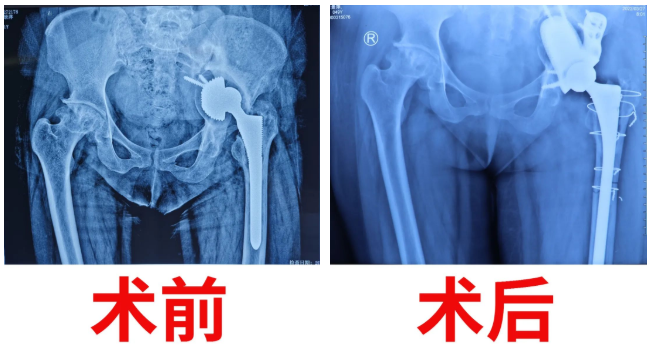

患者在14年前由于“股骨頭壞死”在當?shù)蒯t(yī)院實施了“左側(cè)髖關節(jié)置換術”。6年前逐漸感覺左側(cè)髖關節(jié)越來越不舒服,走路時跛行,癥狀越來越重,病痛折磨無法忍受,嚴重影響日常生活。由于病情嚴重和手術技術難度較大,輾轉(zhuǎn)多家醫(yī)院“碰壁”后,抱著一線希望慕名來到佳木斯大學宏大醫(yī)院找副院長、骨科主任喬建民就診,想徹底解決“關節(jié)之痛”。經(jīng)喬院長詳細詢問病史、查體及輔助檢查,結(jié)合多年臨床經(jīng)驗,診斷為“左人工髖關節(jié)置換術后髖臼松動”(此病例為Paprosky分型ⅢB型,極嚴重型的髖臼缺損),并收其入院準備手術治療。

手術前骨科醫(yī)護人員多次對該患者進行心理疏導,解除患者疑慮。經(jīng)過了縝密的術前準備后,患者被送進了手術室。在麻醉科、手術室的通力配合下,歷經(jīng)4小時的艱苦鏖戰(zhàn),手術終于完成。由于患者髖臼假體位置上移進入盆腔,原髖臼處缺損、不規(guī)則增生、狹窄,手術又不能破壞僅存的少量髖臼骨質(zhì),導致假體取出極其困難;術中必需將股骨(大腿骨)劈開后將原柄取出,并用術前準備的加長柄加鋼絲捆扎固定;缺損后可利用的骨質(zhì)減少,假體要用極少的骨質(zhì)空間準確固定非常困難,角度位置稍有移動,假體將無法牢固固定;假體上移至少4cm,多年肌肉神經(jīng)攣縮,將假體復位于原來的髖臼,使雙下肢等長非常困難,可能造成新的髖臼骨折、肌肉斷裂、神經(jīng)損傷。當戰(zhàn)勝了手術中遇到的種種困難和挑戰(zhàn),成功完成一臺幾乎不可能完成的手術后,骨科團隊露出了勝利的微笑。

在骨科醫(yī)護團隊的悉心照顧和鼓勵下,術后復查顯示假體植入非常理想,患者髖臼骨缺損填補滿意、關節(jié)假體復位滿意,同時也成功地消除了肢體不等長的這個差距,疼痛感完全消失,髖關節(jié)各個方向被動活動基本達到要求?;颊呤中g當天就坐起了身,術后第10日即可下床扶柺慢行。